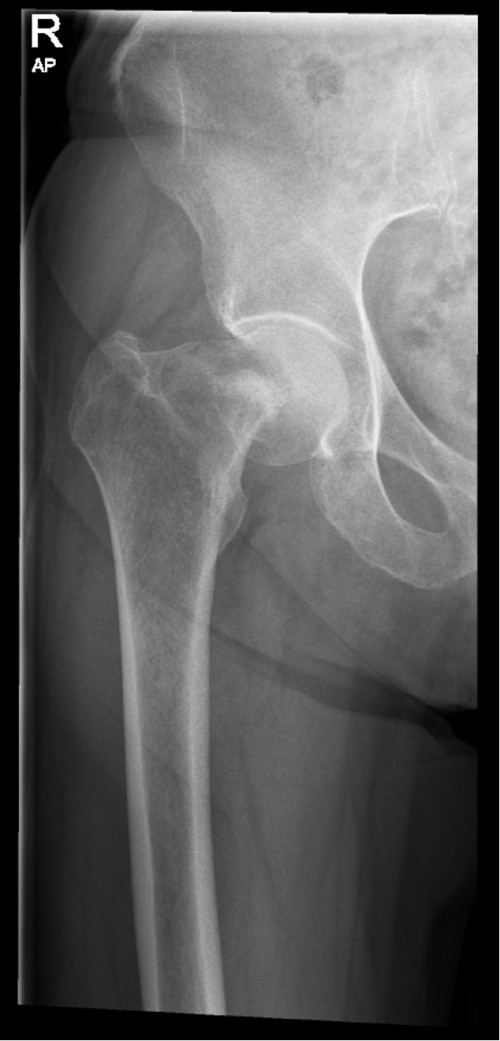

Röntgen Oberschenkel rechts a.p.